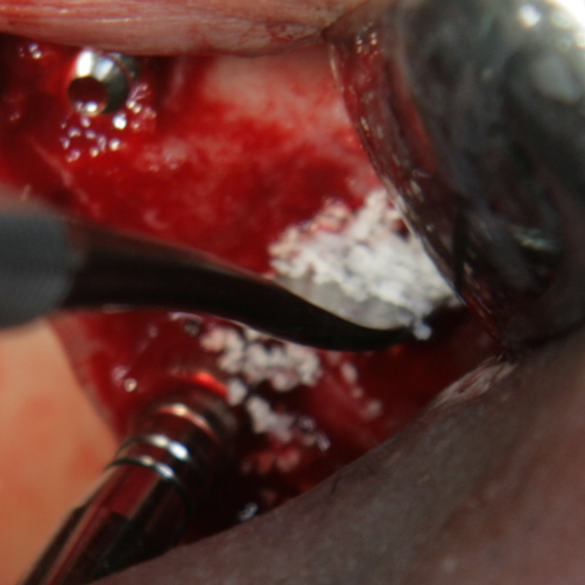

Отворен максиларен синус в началото на интервенцията. Случаят е интересен със следното - твърде атипична форма на трепанационния отвор. На какво се дължи на това - на лошо планиране на оперативния достъп или на нещо друго? Дължи се на факта, че отначало въпросната намеса беше планирана като балонен синуслифт; за съжаление обаче мембраната на синуса се разкъса и надуването на балона стана невъзможно.